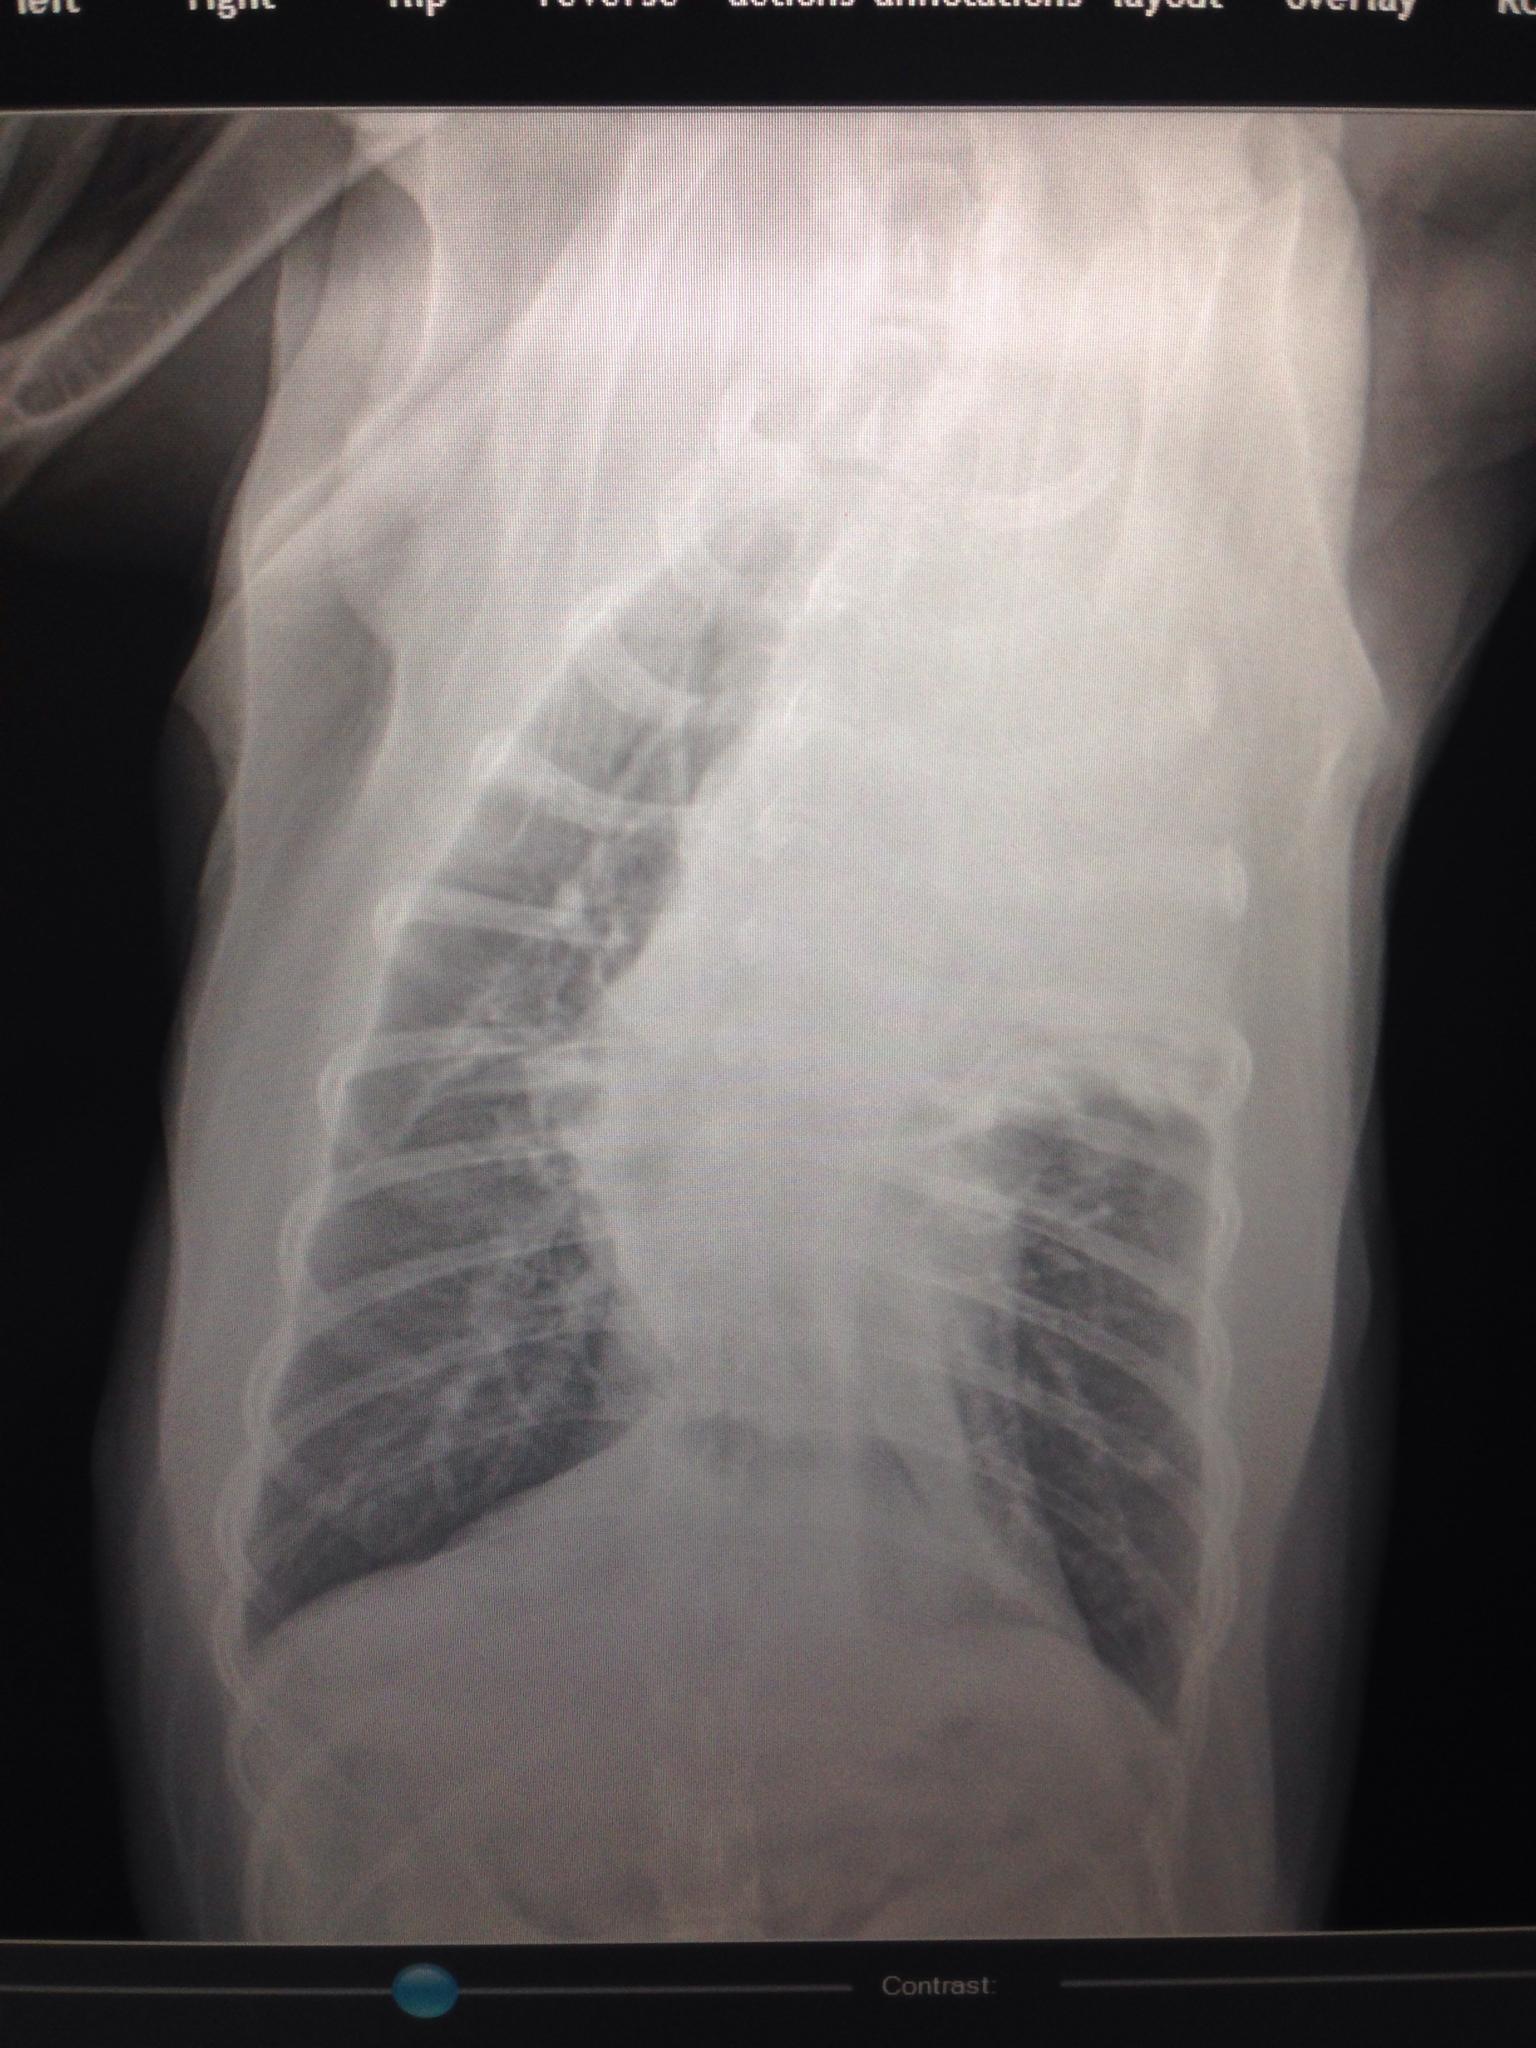

A 9-year-old SF Golden retriever was presented for evaluation of coughing and lethargy. On survey radiographs a left cranial lung mass was evident.

Left cranial lung mass was noted which was significantly hypoechoic and irregular with some cavitation. FNAs were performed without complication. Peripheral air entrapment was noted, which is indicative of lung origin. This may be resectable. CT evaluation would be ideal.